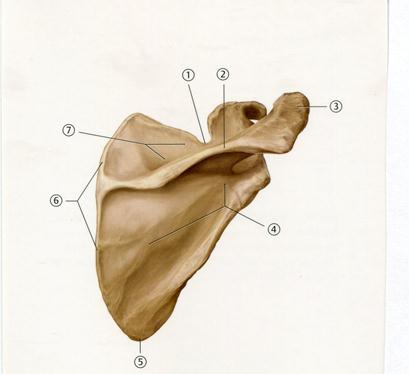

Е. Үлкен бөксе

42. Төменде көрсетілген суреттегі белгіленген №5 анатомиялық құрылымды атаңыз.

D. Медиальді айдаршық буын беті

E. Шонданай төмпегі

48. Төменде көрсетілген суреттегі белгіленген № 4 анатомиялық құрылымды атаңыз.

А. Акромиальді өсінді